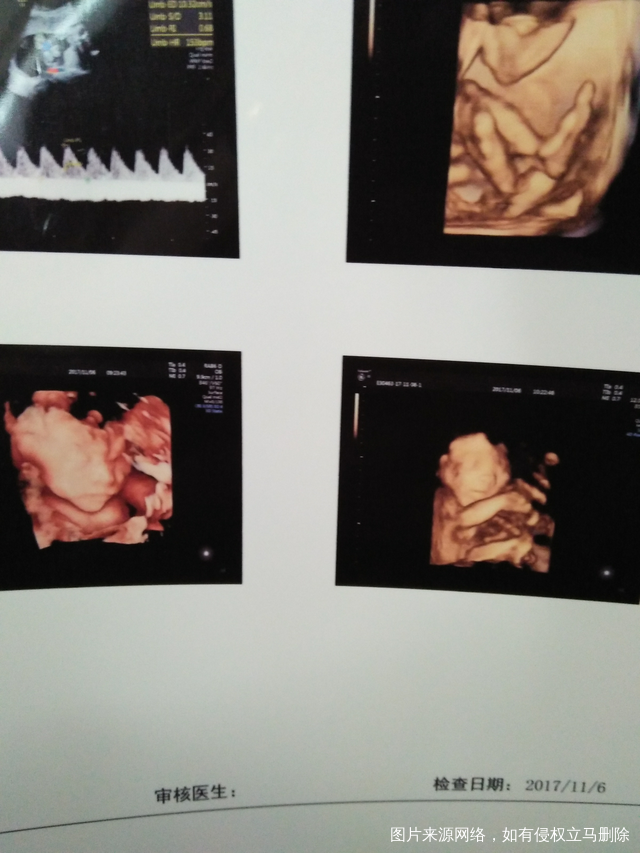

今天做的四维跟她姐姐好像

2017-11-06 11:43:16